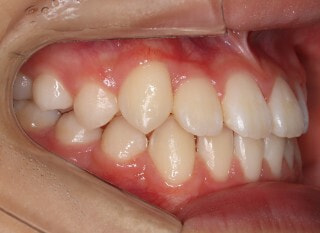

小児期第二段階

開始時